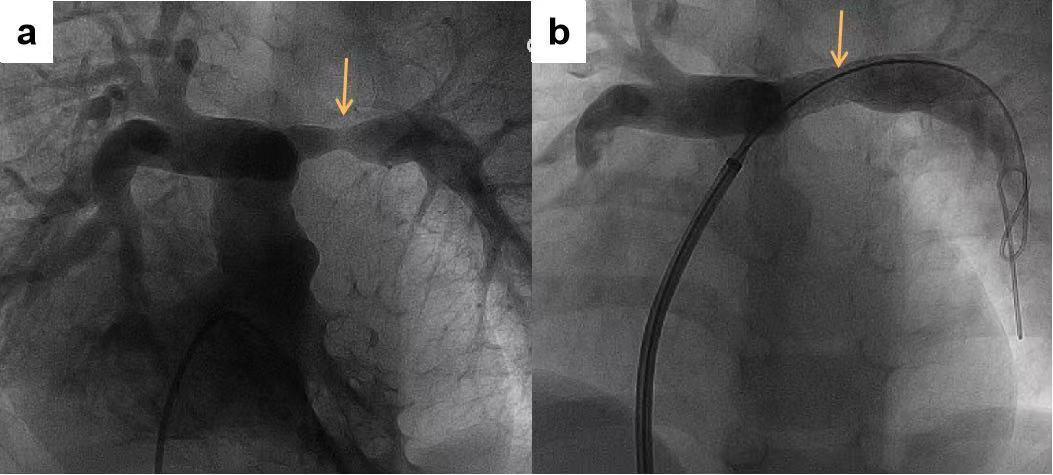

7月13日,两名患儿的手术在全麻下进行,通过股静脉穿刺,将可降解铁基支架通过导管植入狭窄的左肺动脉处,2毫米的支架张开成8毫米直径,撑住血管,植入后即刻心导管及造影检查显示,支架位置及形态良好,肺动脉狭窄解除满意,右心室压力显著降低,达到预期治疗效果。

术前(a)肺动脉狭窄处在术后(b)可见明显畅通与缓解